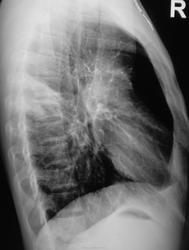

Прошло 3 месяца, и сегодня, фтизиатр прислал на «контроль», взятого на заметку.

Стало ясно, что линейная томография в данном случае не повредит.

Какое мнение будет после томографии у уважаемых коллег?

Формально фтизиатры поставят диагноз инфильтративный туберкулез S6 правого легкого, фаза распада. Но, я не зря спросил про возраст больного. У молодых людей нижнедолевой туберкулез особенно в 6 сегменте часто связан с поражением внутригрудных лимфатических узлов. Пути распространения инфекции лимфобронхогенное. Подтверждением этого является обнаружение при бронхоскопии различных форм активного туберкулеза (инфильтративный, язвенный и лимфобронхиальный свищ). При бронхоскопии у больного могут найдут специфическое поржение бронхов. Лимфогенный путь распространения напоминает раковый лимфангиит . О лимфогенном распространении инфекции указывает прединфильтратная сетка, которую хорошо видно на рентгенограммах. О поражении лимфатических бронхопульмональных узлов свидетельствует вовлечение в процесс плевральных листков в виде воспалительного уплотнения междолевой плевры, а также наклонность к раннему образованию распада. Известно,что у взрослых трудно выявить изменения со стороны ВГЛУ, так как они не часто достигают той величины, как у детей. Умеренно выраженное увеличение бронхопульмональных л/у на КТ диагностируется только при контрастировании. Таким образом, предварительный патогенетический диагноз звучал бы так : туберкулез внутригрудных лимфатических узлов бронхопульмональной группы справа, осложненный бронхолегочным поражением в S6 с распадом. Необходимо построить патогенетический диагноз, так как специфические изменения в лимфатических узлах требуют более длительного лечения. Такова моя точка зрения на диагноз у представленного пациента. С уважением Ваш NIkolas